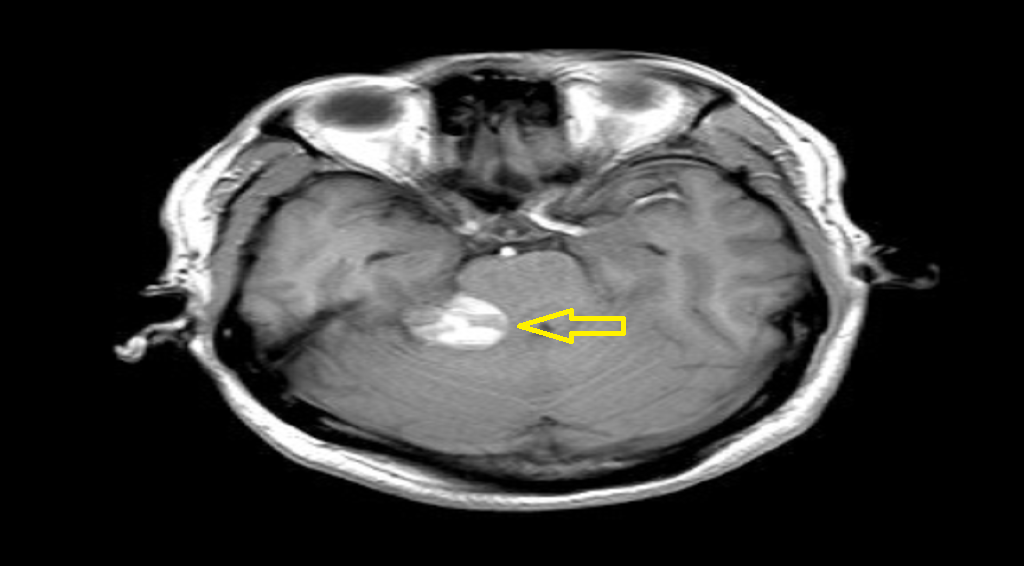

■ 袁女士颅内肿瘤位于左侧桥小脑角区,约6*4*4cm大小,占位效应明显,手术指征明确,其颅内肿瘤与周围血管及神经包裹密切,且体积巨大,经过长达六小时手术,肿瘤被顺利切除。

(术前)

(术后)